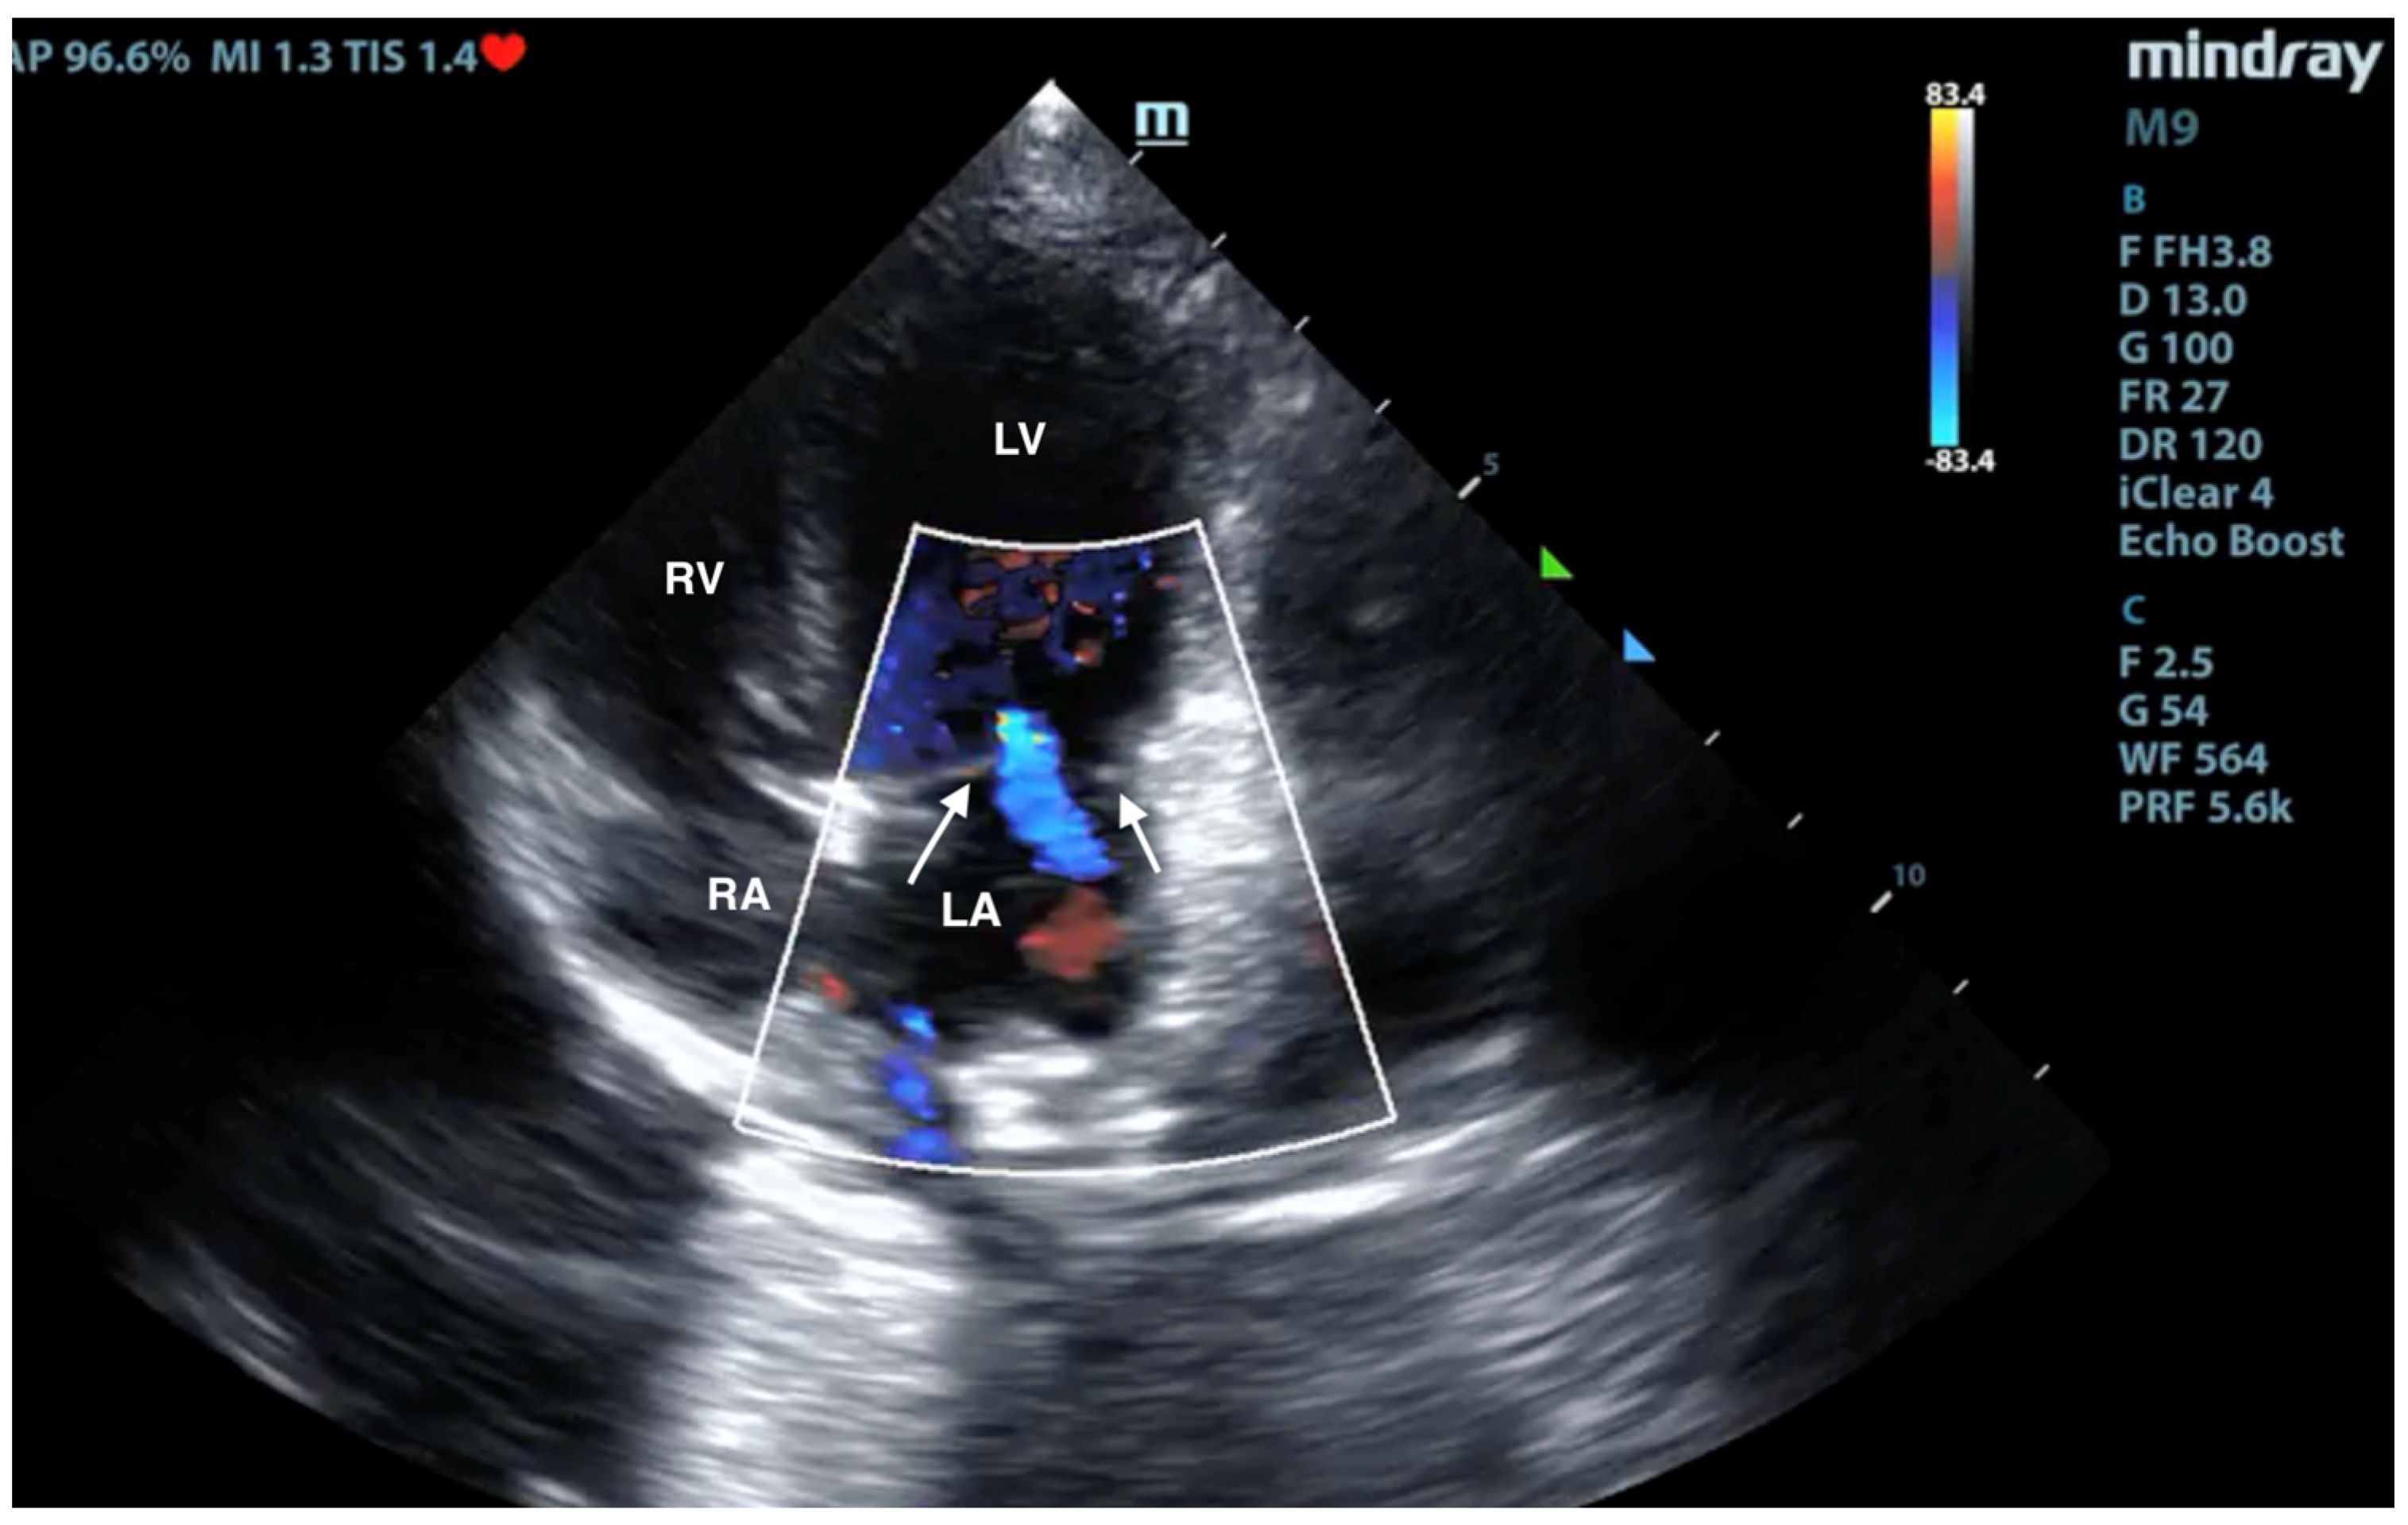

3.3. X-ray and Ultrasound Examination

No pathological changes were detected in the lung parenchyma image in the X-ray (Figure 1 and Figure 2). The ultrasound examination revealed in all views a normal, aerated lung pattern. The pleural line was intact, and A-line artifacts were present (Figure 3). The sliding sign was also observed. Echocardiography revealed a mild thickening of the mitral valve leaflets and a slight regurgitation (Figure 4) of this valve. The size of the heart chambers was within the normal range, and myocardial contractility was normal.

Figure 4.

Scan from phased array probe obtained during echocardiography examination performed by a board-certified echocardiography specialist. Mild thickening of the mitral valve and slight regurgitation are visible. The white arrows indicate mitral valve leaflets. LA—left atrium, LV—left ventricle, RA—right atrium, RV—right ventricle.